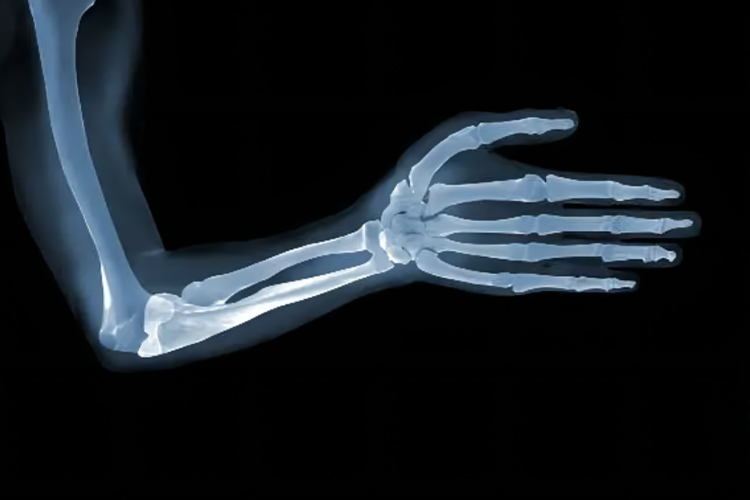

X光指X线影像,能够透过人体不同组织,经过处理得到人体影像。

正常手臂的X线多可表现为密度均匀,结构完整的的影像。

X线有很强的贯穿本领,当一束强度大致均匀的X线投照到手臂上时,正常人多可表现为密度均匀的致密影,外缘清楚,在骨干中部最厚,越近两端越薄,骨皮质外面和里面均覆有骨膜,前者为骨外膜,后者为骨内膜。骨干中央为骨髓腔,充满骨髓。

手臂主要包括肱骨、桡骨、尺骨、腕骨等,如手臂受到撞击等外力,可能会出现骨折,表现为局部肿胀、疼痛、活动受限等症状,应及时到医院就诊,行复位及固定治疗。